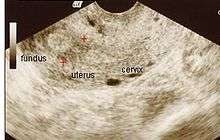

The history of a pregnancy event followed by a D&C leading to secondary amenorrhea or hypomenorrhea is typical. Hysteroscopy is the gold standard for diagnosis.[8] Imaging by sonohysterography or hysterosalpingography will reveal the extent of the scar formation. Ultrasound is not a reliable method of diagnosing Asherman's Syndrome. Hormone studies show normal levels consistent with reproductive function.